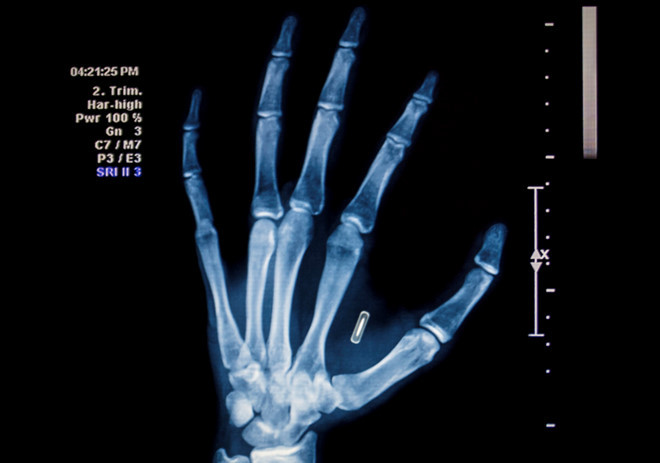

Việc cấy ghép chip cho nhân viên cũng không phải quá mới mẻ. Năm 2017, công ty Three Square Market ở Wiconsin, Mỹ đã cấy ghép chip cho hơn 80 nhân viên. Các chip RFID nhỏ bằng kích cỡ hạt gạo được cấy vào tay để nhận diện, cho phép nhân viên vận hành máy móc đúng trách nhiệm của mình. Thú vị ở chỗ, Three Square bán máy bán hàng tự động nhưng đồng thời cũng là nhà gia công cấy ghép chip.

Jowan Osterlund từ công ty Biohax Thụy Điển, đang cầm một con microchip cấy ghép, tương tự với loại được cấy cho các công nhân ở Vườn ươm trung tâm Stockholm. Ảnh: Engadget.